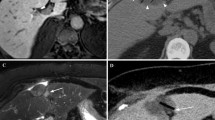

All patients underwent pretreatment blood chemistry testing and imaging evaluation. We considered total and fractionated bilirubin, Quick’s time, INR, albumin, platelets, ammonia, α-fetoprotein (αFP), and ferritin and hepatitic markers. We obtained an ECG for each patient. Before the cryoablation procedure all patients also underwent upper abdominal US imaging (ATL HD 5000; Philips, Best, Netherlands) and 64-multislice CT scan (LightSpeed 64 CT; GE Medical Systems, Milwaukee, WI, USA) with the three-phase technique (30, 65, and 180 s) following intravenous injection of a 120 ml bolus of iodinated contrast medium (300 mgI/ml; Ultravist, Schering) and a 20 ml bolus of physiologic solution (Figs. 1 and 2). Scanning parameters were 1 s gantry rotation time, 1.25 mm collimation with the possibility of retroreconstruction at 0.6 mm, 360 mA, and 120 kV.

Each lesion received a treatment cycle of freezing (−60°C), heating (up to 70°C), and refreezing to avoid tumor cell seeding and the duration of the procedure was based on growth of the iceball relative to the tumor (mean, 15 min; range, 10–18 min). Limited unenhanced CT scans were obtained approximately every 3 min during the first freezing time using 1.25 mm collimation to monitor growth of the iceball. CT was used to accurately monitor iceball size and location and help predict subsequent cell death (Figs. 4 and 5) [16, 17]. We used a single cycle (formed by freezing-heating-freezing) because we wanted to demonstrate the efficacy of single and short-time treatment in accordance with in vitro studies by Tacke et al. who observed no differences in maximum diameter among three freezing cycles that were performed at different locations in the same liver with direct visual measurement [14].

Treatment success was defined as extension of the iceball 5 mm beyond the tumor margin and absence of arterial contrast enhancement during postprocedural CT control after cryoprobe removal (Fig. 6). Once complete tumor ablation had been achieved, all patients were included in the follow-up program. At 1, 3, and 6 months patients underwent alkaline phosphatase, total and fractionated bilirubin, transaminases, γ-glutamyl transpeptidase (γGT), carcinoembryonic antigen (CEA), albumin, Quick’s time and INR, complete blood count (CBC), and platelet and αFP testing. The Child-Pugh class was reviewed. At 1, 3, and 6 months patients underwent triphasic CT for evaluation of the ablation zone and detection of local tumor progression and/or new HCC lesions. We distinguished two types of recurrence disease: local tumor progression and new HCC lesions. The first was the presence of neoplastic tissue within the same liver segment at the margin of a treated HCC nodule and the second was the development of nodules in a different liver segment.

Our initial experience was treating four patients with HCC. The maximum diameter of the four lesions ranged from 1.8 to 3 cm. Cryoablation was technically successful in all patients at the end of the procedure. No repeat treatment was needed because there was no contrast enhancement in postprocedural CT control, as the diameters of the iceballs obtained ranged from 3 to 4 cm with an extension of the iceball 5 mm beyond the tumor margin in all cases. Each HCC received a treatment cycle of freezing, heating, and refreezing; and the duration of the procedure was based on growth of the iceball relative to the tumor (mean, 15 min; range, 10–18 min). The number of cryoprobes used during ablation was two or three on the basis of tumor diameter. The iceball Hounsfield unit (HU) value was 18–22, obtained with a region of interest of 2 mm localized in the area between the frozen/unfrozen edge and the cryoprobe.

No deaths or major complications (no hemorrage found in any case) occurred during the procedures, and no cases of neoplastic seeding have been observed to date. During follow-up two patients developed disease recurrence. One patient developed local tumor progression visualized as perilesional contrast enhancement at first CT follow-up control at 1 month (Fig. 7). The same patient was subjected to surgical resection of another HCC lesion 2 years previously and to RFA 1 year previously. The second patient developed a new HCC that was detected 6 months after the procedure. No local tumor or new lesions were found in the other 2 patients.